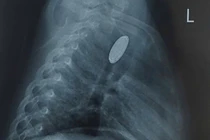

Nội soi thực quản cho thấy, niêm mạc thực quản phù nề, mất mạng lưới mạch bình thường, xuất hiện nhiều vòng đồng tâm, rãnh dọc sâu dọc theo chiều dọc thực quản, kèm theo các chấm trắng nhỏ rải rác trên bề mặt niêm mạc. Các tổn thương này là hình ảnh đặc trưng của viêm thực quản tăng bạch cầu ái toan. Bác sĩ đã sinh thiết lấy mẫu mô thực quản để làm giải phẫu bệnh và kết quả phù hợp với viêm thực quản tăng bạch cầu ái toan. Cùng với đó, kết quả nội soi dạ dày có viêm teo dạ dày (C1).

Hình ảnh nội soi thực quản của bệnh nhân/Ảnh BV medlatec